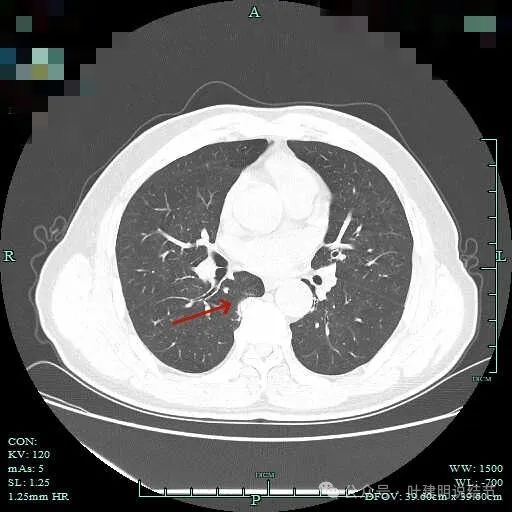

病仍明显,从上到下,觉得应该是成片的。

表面不平毛刺,实性密度为主。

微小血管有,但无异常增粗。

病灶实性,边缘不光滑。

实性密度,片状,条状。

病灶实性,缺乏膨胀性。